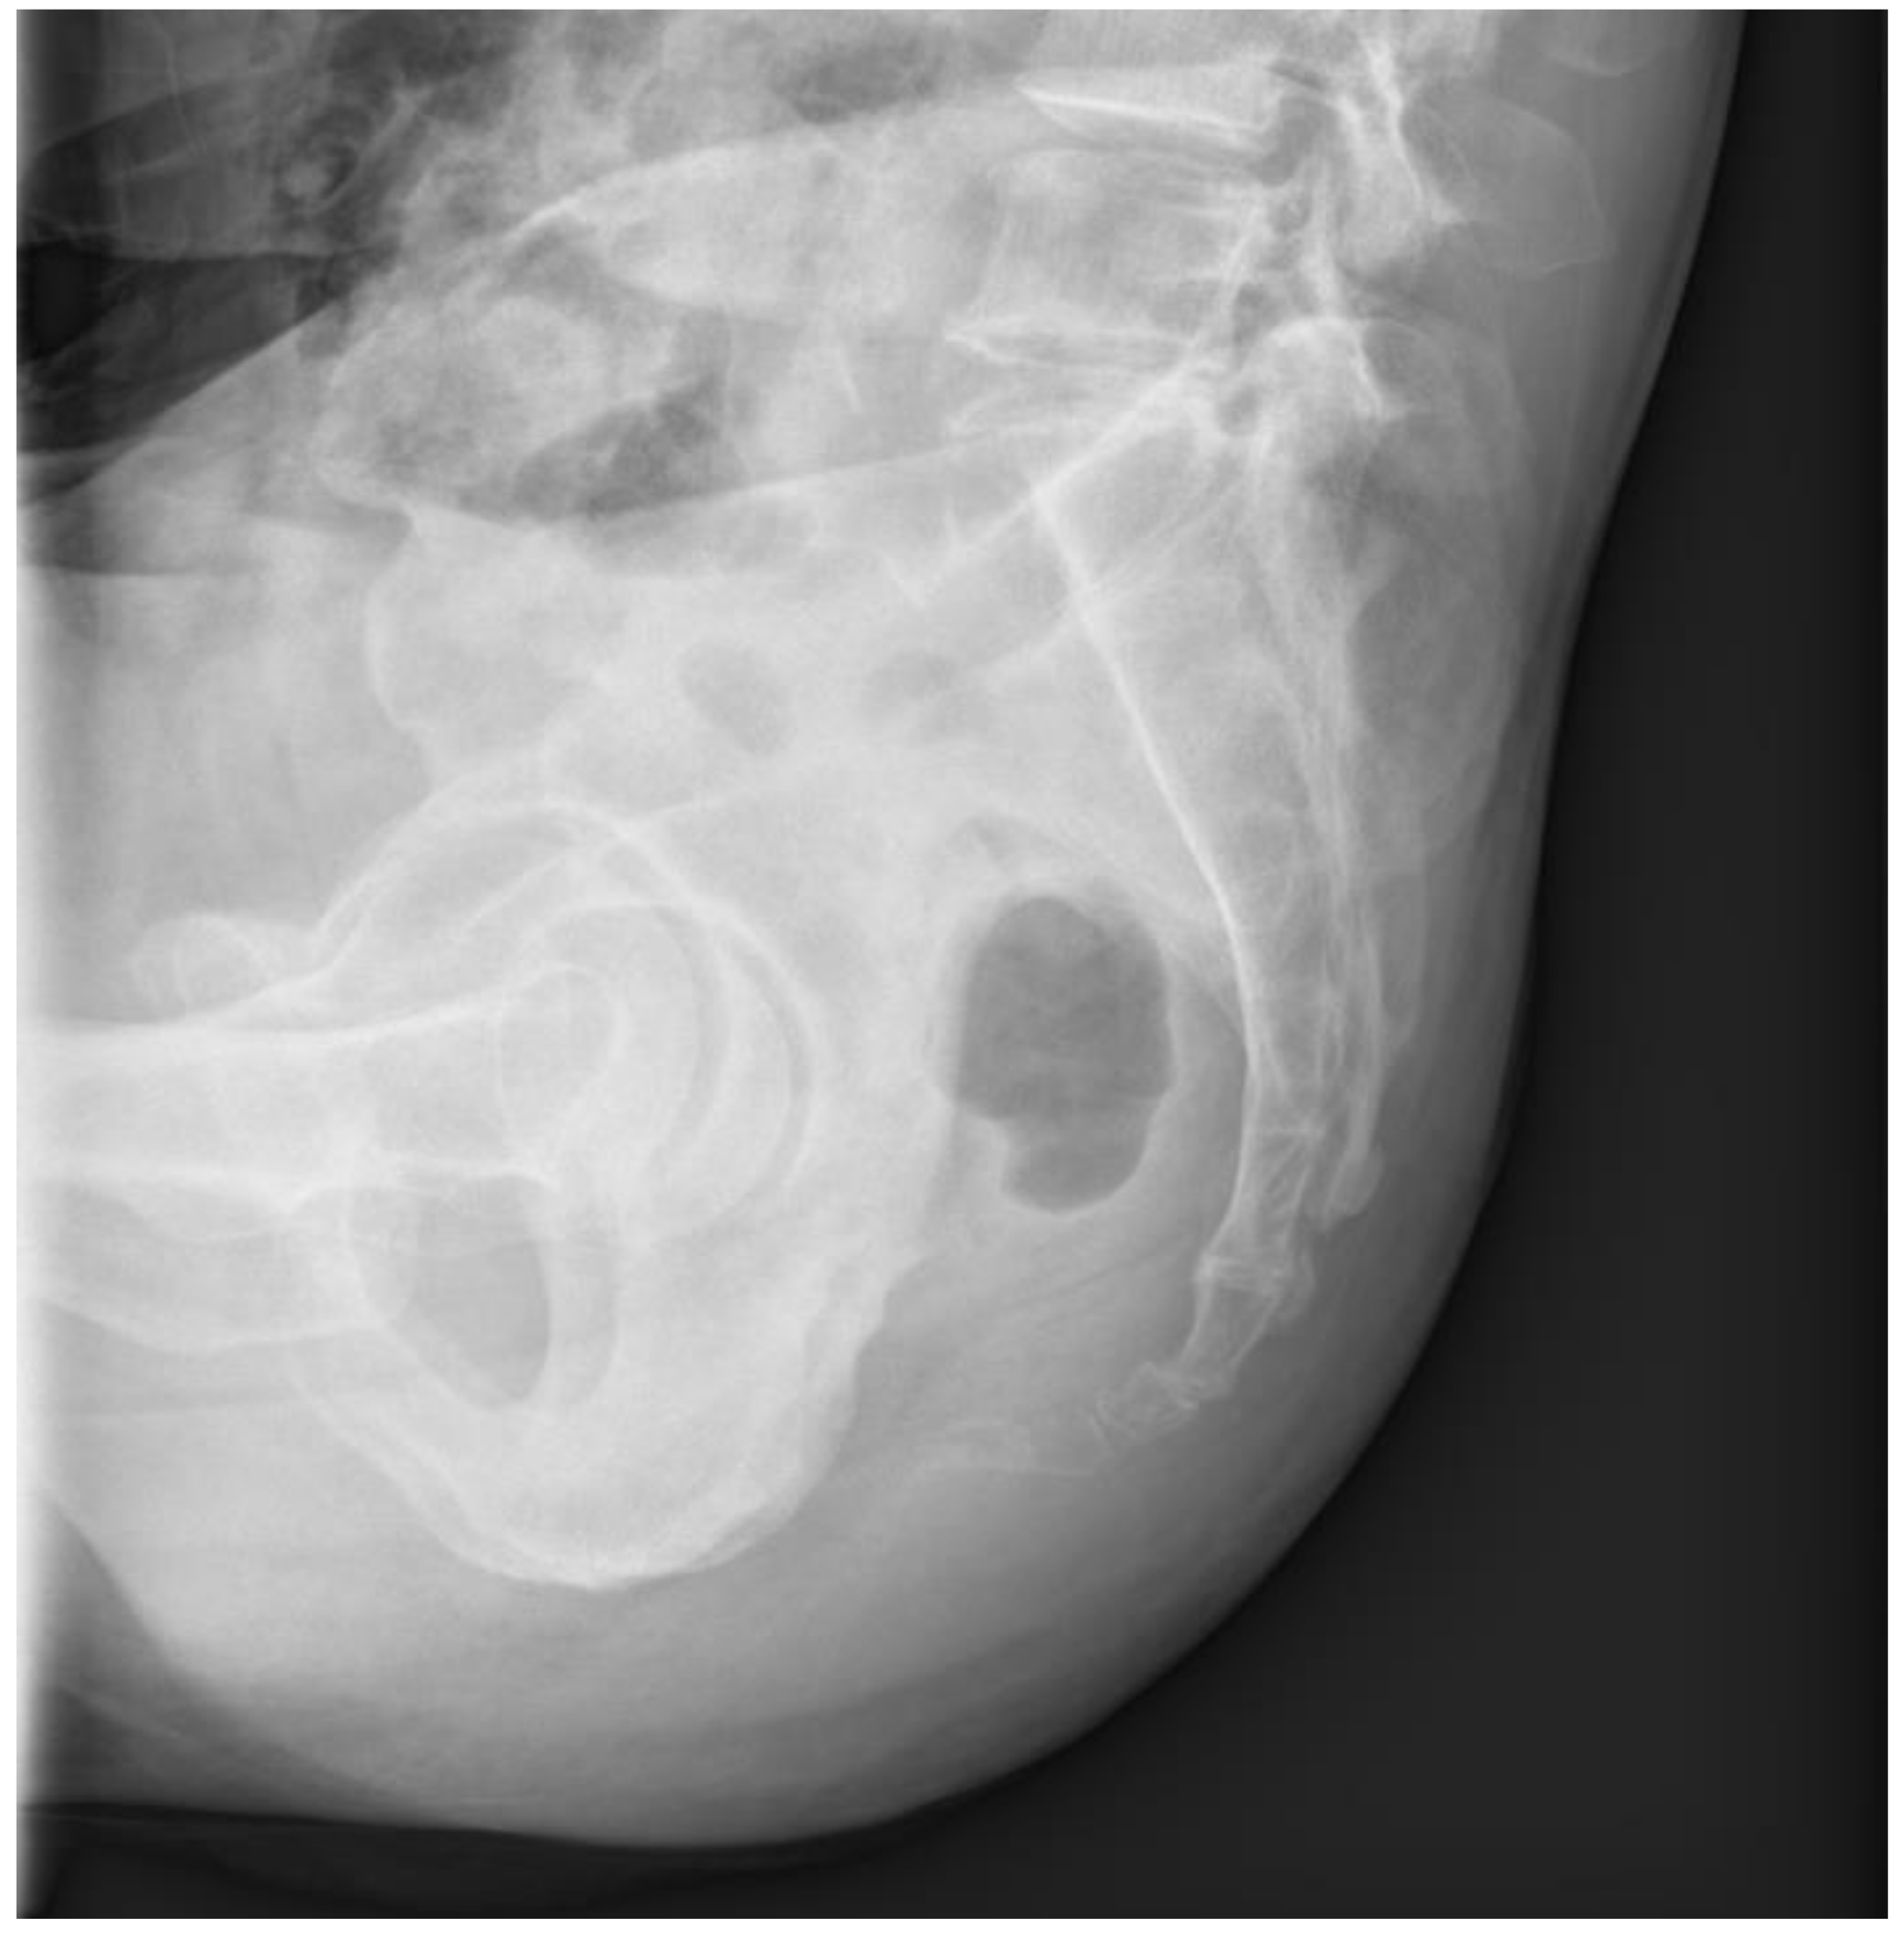

At the 6-month follow-up, the sacrococcygeal joint showed good alignment without any additional complications (Figure 6).

Figure 6. Plain lateral radiography performed six months after the operation. The sacrococcygeal joint maintained good alignment.